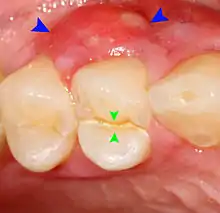

- Radiographs utilized to find dental caries and bone loss laterally or at the apex.

Decay (green) with apical abscess (blue)

Gutta-percha point indicating abscess origin